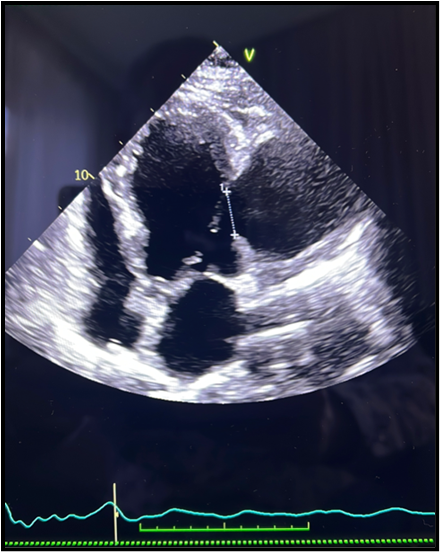

Transthoracic echocardiography dated 2/08/2024. – Enlarged left ventricle, hypertrophy of the left ventricular muscle and interventricular septum, impaired total left ventricular systolic function with LVEF of 40%, normal right ventricular systolic function, structure and function of the valves without significant deviations, in communication with the left ventricular lateral wall a pseudoaneurysm measuring 70 x 55 mm (SAX) and 71 x 58 mm (A4C) with gates of about 23 mm wide, through the gates of the aneurysm visible systolic and diastolic flow (Figure 2).

Figure 2: Echocardiography: large left ventricular pseudoaneurysm with free wall rupture